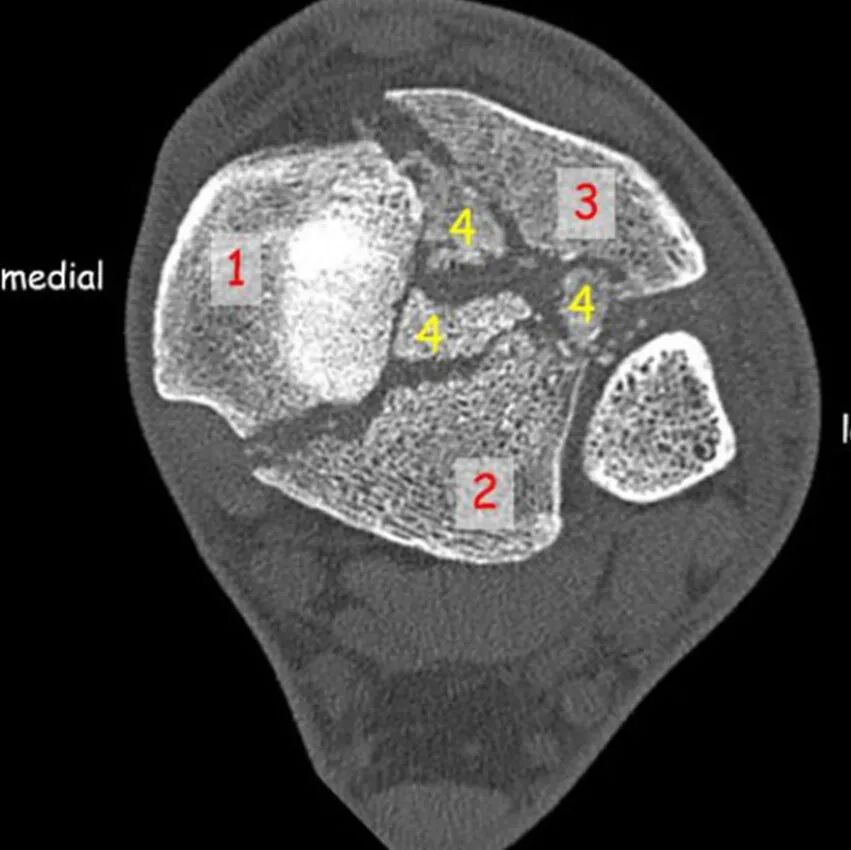

显露整个后Pilon骨折的另一种选择是采用改良后内侧入路,该入路无需广泛牵开软组织即可从内侧向外侧显露骨折部位。Pilon骨折的横截面解剖显示,手术入路位于跟腱和拇长屈肌内侧(下图所示):

切口(图A)始于跟腱跟骨止点近端,距其内侧边缘1cm,向近端延伸12cm。切开浅筋膜,显露跟腱和比目鱼肌远端部分,将跟腱向外侧牵开,注意保护其腱鞘,此时可能会遇到附着于跟腱最深部的比目鱼肌纤维,将其与跟腱一同牵开,将胫后肌腱主体向内侧牵开。我们未将后柱显露至胫骨中远端1/3交界处以上。钝性分离至构成浅后筋膜室底部的横肌间隔(图B),该间隔分隔浅后筋膜室和深后筋膜室,在中线纵向切开间隔,进入深后筋膜室,可见拇长屈肌腱及其肌腹。此时可见胫神经位于拇长屈肌内侧缘(图C),分离拇长屈肌内侧缘与胫神经之间的间隙,将拇长屈肌向外侧牵开,进一步牵开后可显露胫骨后干骺端全貌、踝关节后囊、后下胫腓联合以及内踝和外踝后方(图D)。